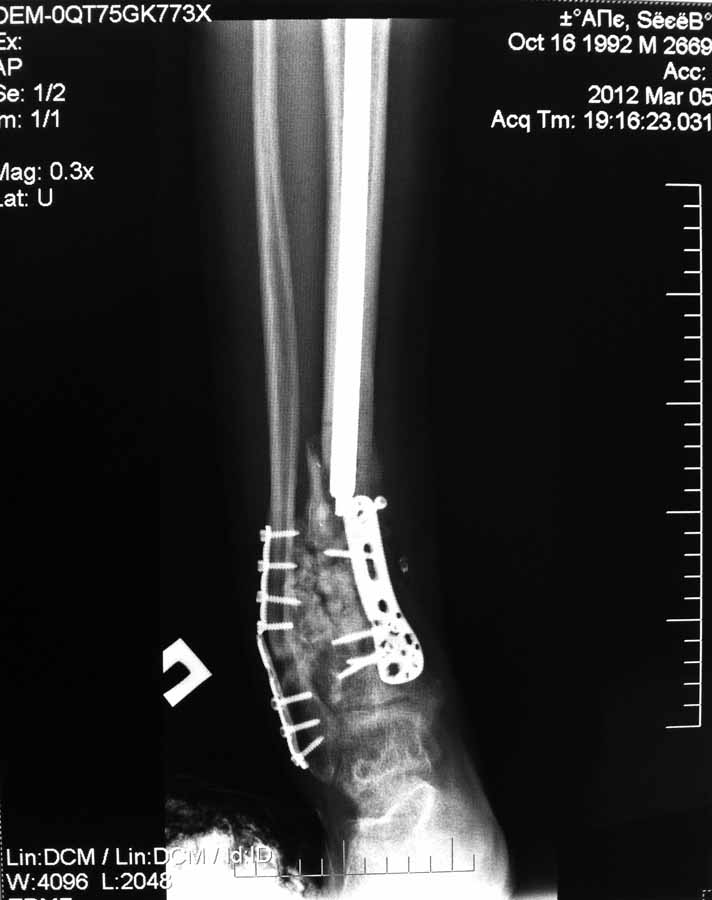

Re: Несращение дистального отдела костей голени

Вчера не вышло выслать все фото. Последние снимки более более драматичные, как раз с куском проксимального стержня и пластиной что не к месту!